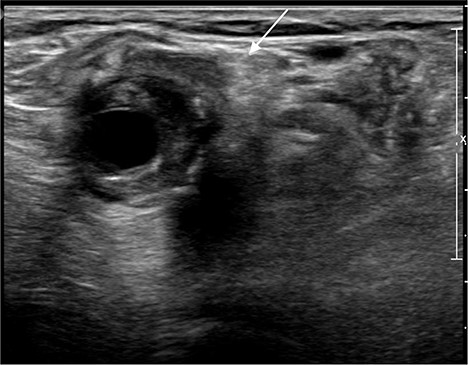

A 92-year-old female, independent from home, presented after multiple falls due to a four-month history of left foot drop. The foot drop had gradually worsened to the point that there was complete paralysis of ankle dorsiflexion and was associated with significant oedema of the foot. On examination, there was a large pulsatile mass in the popliteal fossa bilaterally. All peripheral pulses were palpable without any signs of ischemia. The most striking examination finding was complete paralysis of left ankle dorsiflexion with 0 out of 5 power. Ultrasound revealed that there were (Fig 1) bilateral popliteal artery aneurysms, which was larger on the left, causing displacement and impingement of the common peroneal nerve at the knee crease (Fig 2). Further computed tomography angiogram demonstrated an unruptured left PAA measuring 22 × 21 mm in maximal dimension over a distance of 24 mm (Fig 3). Intraluminal thrombus was also noted with 60% luminal stenosis. Distally, the arteries were heavily calcified with two-vessel runoff at the ankle. An emergency endovascular repair of the left PAA was performed by using 8 mm × 15 cm and 7 mm × 10 cm Gore Viabahn stents (Fig 4). The stents were deployed after a balloon-angioplasty and adequate decompression of the aneurysm was achieved. The postoperative period was uneventful, and patient’s pre-existing aspirin was continued. The leg and foot oedema improved rapidly over the subsequent few days. At follow-up in 12 weeks, the patient showed some return of motor function of the ankle and was walking with ankle splint. Her left leg remained well perfused with palpable pulses.

Ultrasound image of left popliteal artery aneurysm, causing displacement and impingement of the common peroneal nerve (indicated by the white arrow).